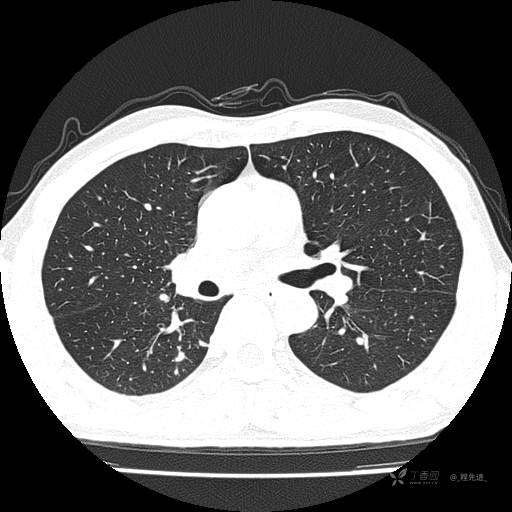

2月特别精彩病例|咳嗽、咳痰20余天,典型病例分享【结果已公布】

患者年龄:51岁

主诉:咳嗽、咳痰20余天

简要病史:20余天前开始出现咳嗽、咳痰症状,阵发性刺激性咳,白色粘痰,不易咳出,无发热,无咯血,无恶心、呕吐等不适,未诊治,咳嗽、咳痰症状持续存在。

体格检查:T:36.3 ℃ P:79 次/分 R:20 次/分 BP:128/64 mmHg,神志清楚,呼吸平稳,双肺呼吸音粗,右下肺闻及细湿性啰音。心率79次/分,节律整齐,各瓣膜听诊区未闻及病理性杂音。腹部未见异常,双下肢无水肿。

辅助检查:我院门诊胸部CT示:如下。心电图:窦性心律;正常心电图。